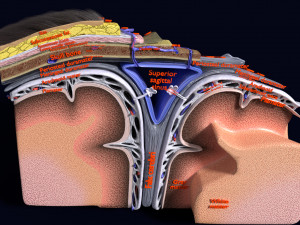

A blend model of brain along with its covering layers (meninges), skull bone and scalp labelled in detail and anatomically precise. The parts depicted are white, gray, pia, arachnoid, dura, bone, skin, fat, aponeurosis, periosteum, falx cerebri and more.